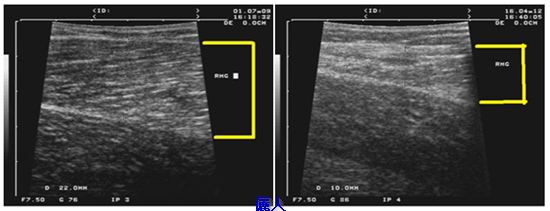

部份切除的肌肉是否已喪失功能? 我們就下病例加以解釋。病例術前的小腿圍是33公分,拿掉部份內腓、外腓及比目魚肌後二個半月,小腿圍縮減為29.5公分。 術前的內腓厚度是19 mm(超音波左圖,白色箭頭內為內腓)。術後二個半月的內腓厚度是11 mm(超音波中圖)。肌肉在超音波下可以看到紋理,當肌肉在收縮時肌肉紋理的角度會變大。病人在術後腳板平放時內腓肌肉紋理是12度(超音波對中圖,黃色間的角度),術後墊腳尖時變為20度(超音波右圖),可見術後的肌肉是有功能的。但如果肌肉部份切除的量較多的話,肌肉功能也可能會受影響。

其他蘿蔔腿的報導追踨時間常常是幾個月而已,我們會長期追踨我們的案例,以下是做完肌肉雕塑手術術前(左)與術後二年九個月(右)的內腓超音波圖。術前是2.2cm,術後是1cm,即使是男性病人,肌肉並沒有長回來或手術造成小腿功能影響。